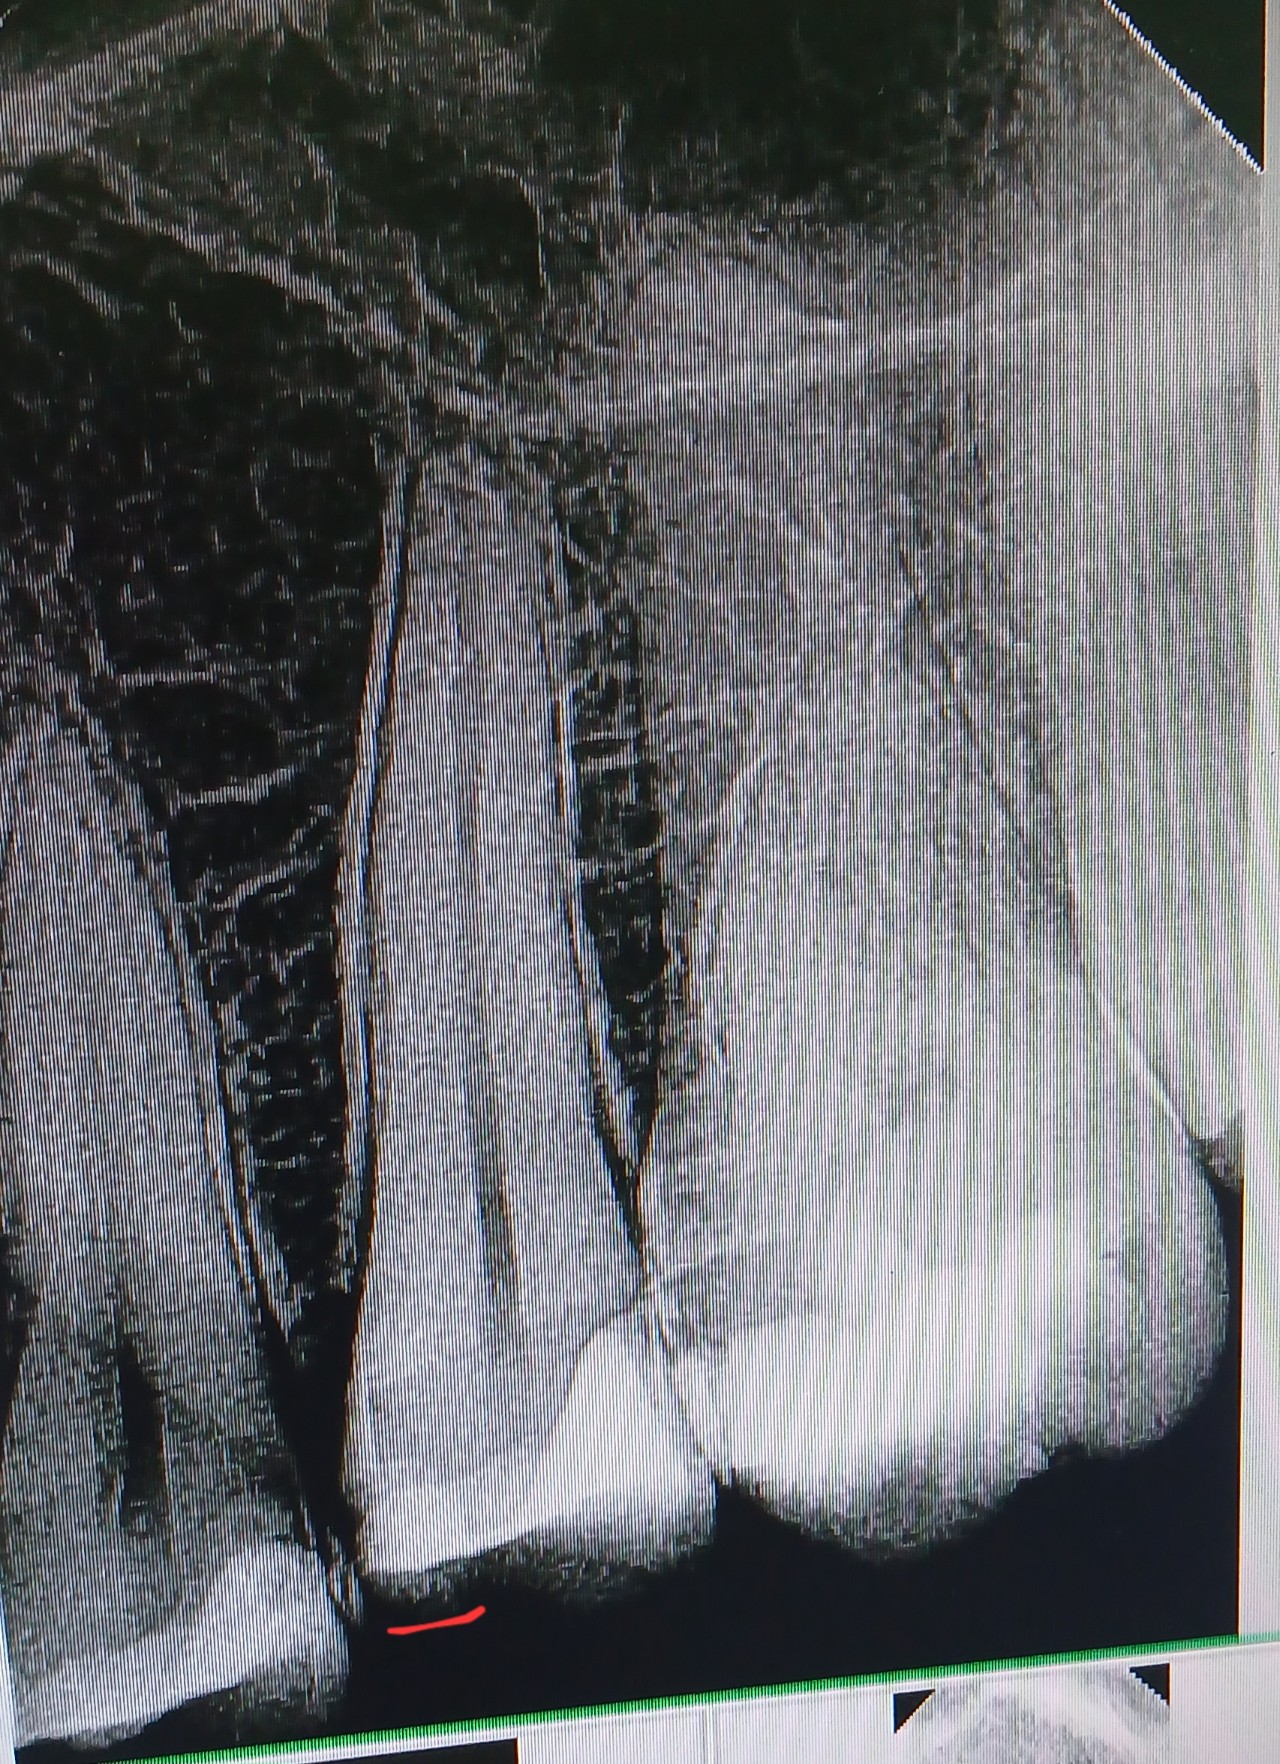

Здравствуйте. Лечила зуб (5ка) месяц назад сбоку, на фото пометила, а с другой стороны 3 года назад лечили. Стоматолог посмотрела снимок, сказала все нормально, пломба далеко от нерва. Но после лечения в этот раз он начал болеть, ноет, а ночью сильнее, удивительно что до лечения вообще не болел. Подскажите почему так?